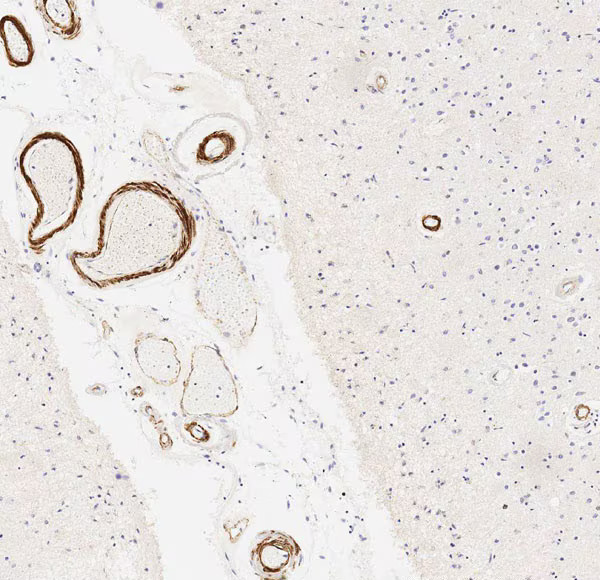

Anti-vascular Amyloid 1-42抗体[mOC31] - Conformation-Specific

描述 兔单克隆抗体[mOC31] to vascular Amyloid 1-42 - Conformation-Specific

经测试应用 适用于: Dot blot, IHC-P, IHC-FrFl

种属反应性 与反应: Mouse, Human

阳性对照 beta Amyloid (Aß) 1-42 IHC-P: FFPE human brain Alzheimer

IHC-P 1/250 - 1/500. Do not perform antigen retrieval.